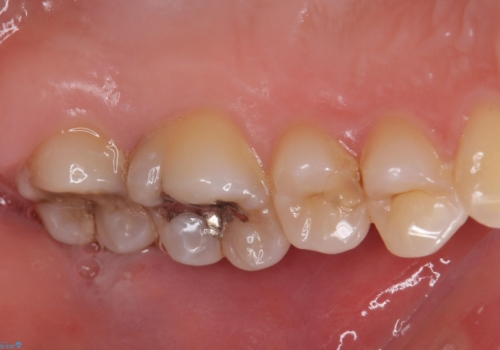

奥歯の虫歯の治療

- 奥歯が虫歯になっていたため治療しました。

手前側の歯は前から見えるため、セラミックの詰め物で治療しました。

奥は高さを取るのが難しかったため薄く作れる金属(ゴールド)で治療しています。

- 合計 26.4万円(内訳:右上7 PGAクラウン 11万円(旧料金)、右上6PGAインレー 7.7万円(旧料金)、右上5 emaxインレー 7.7万円)費用は治療当時の料金となります